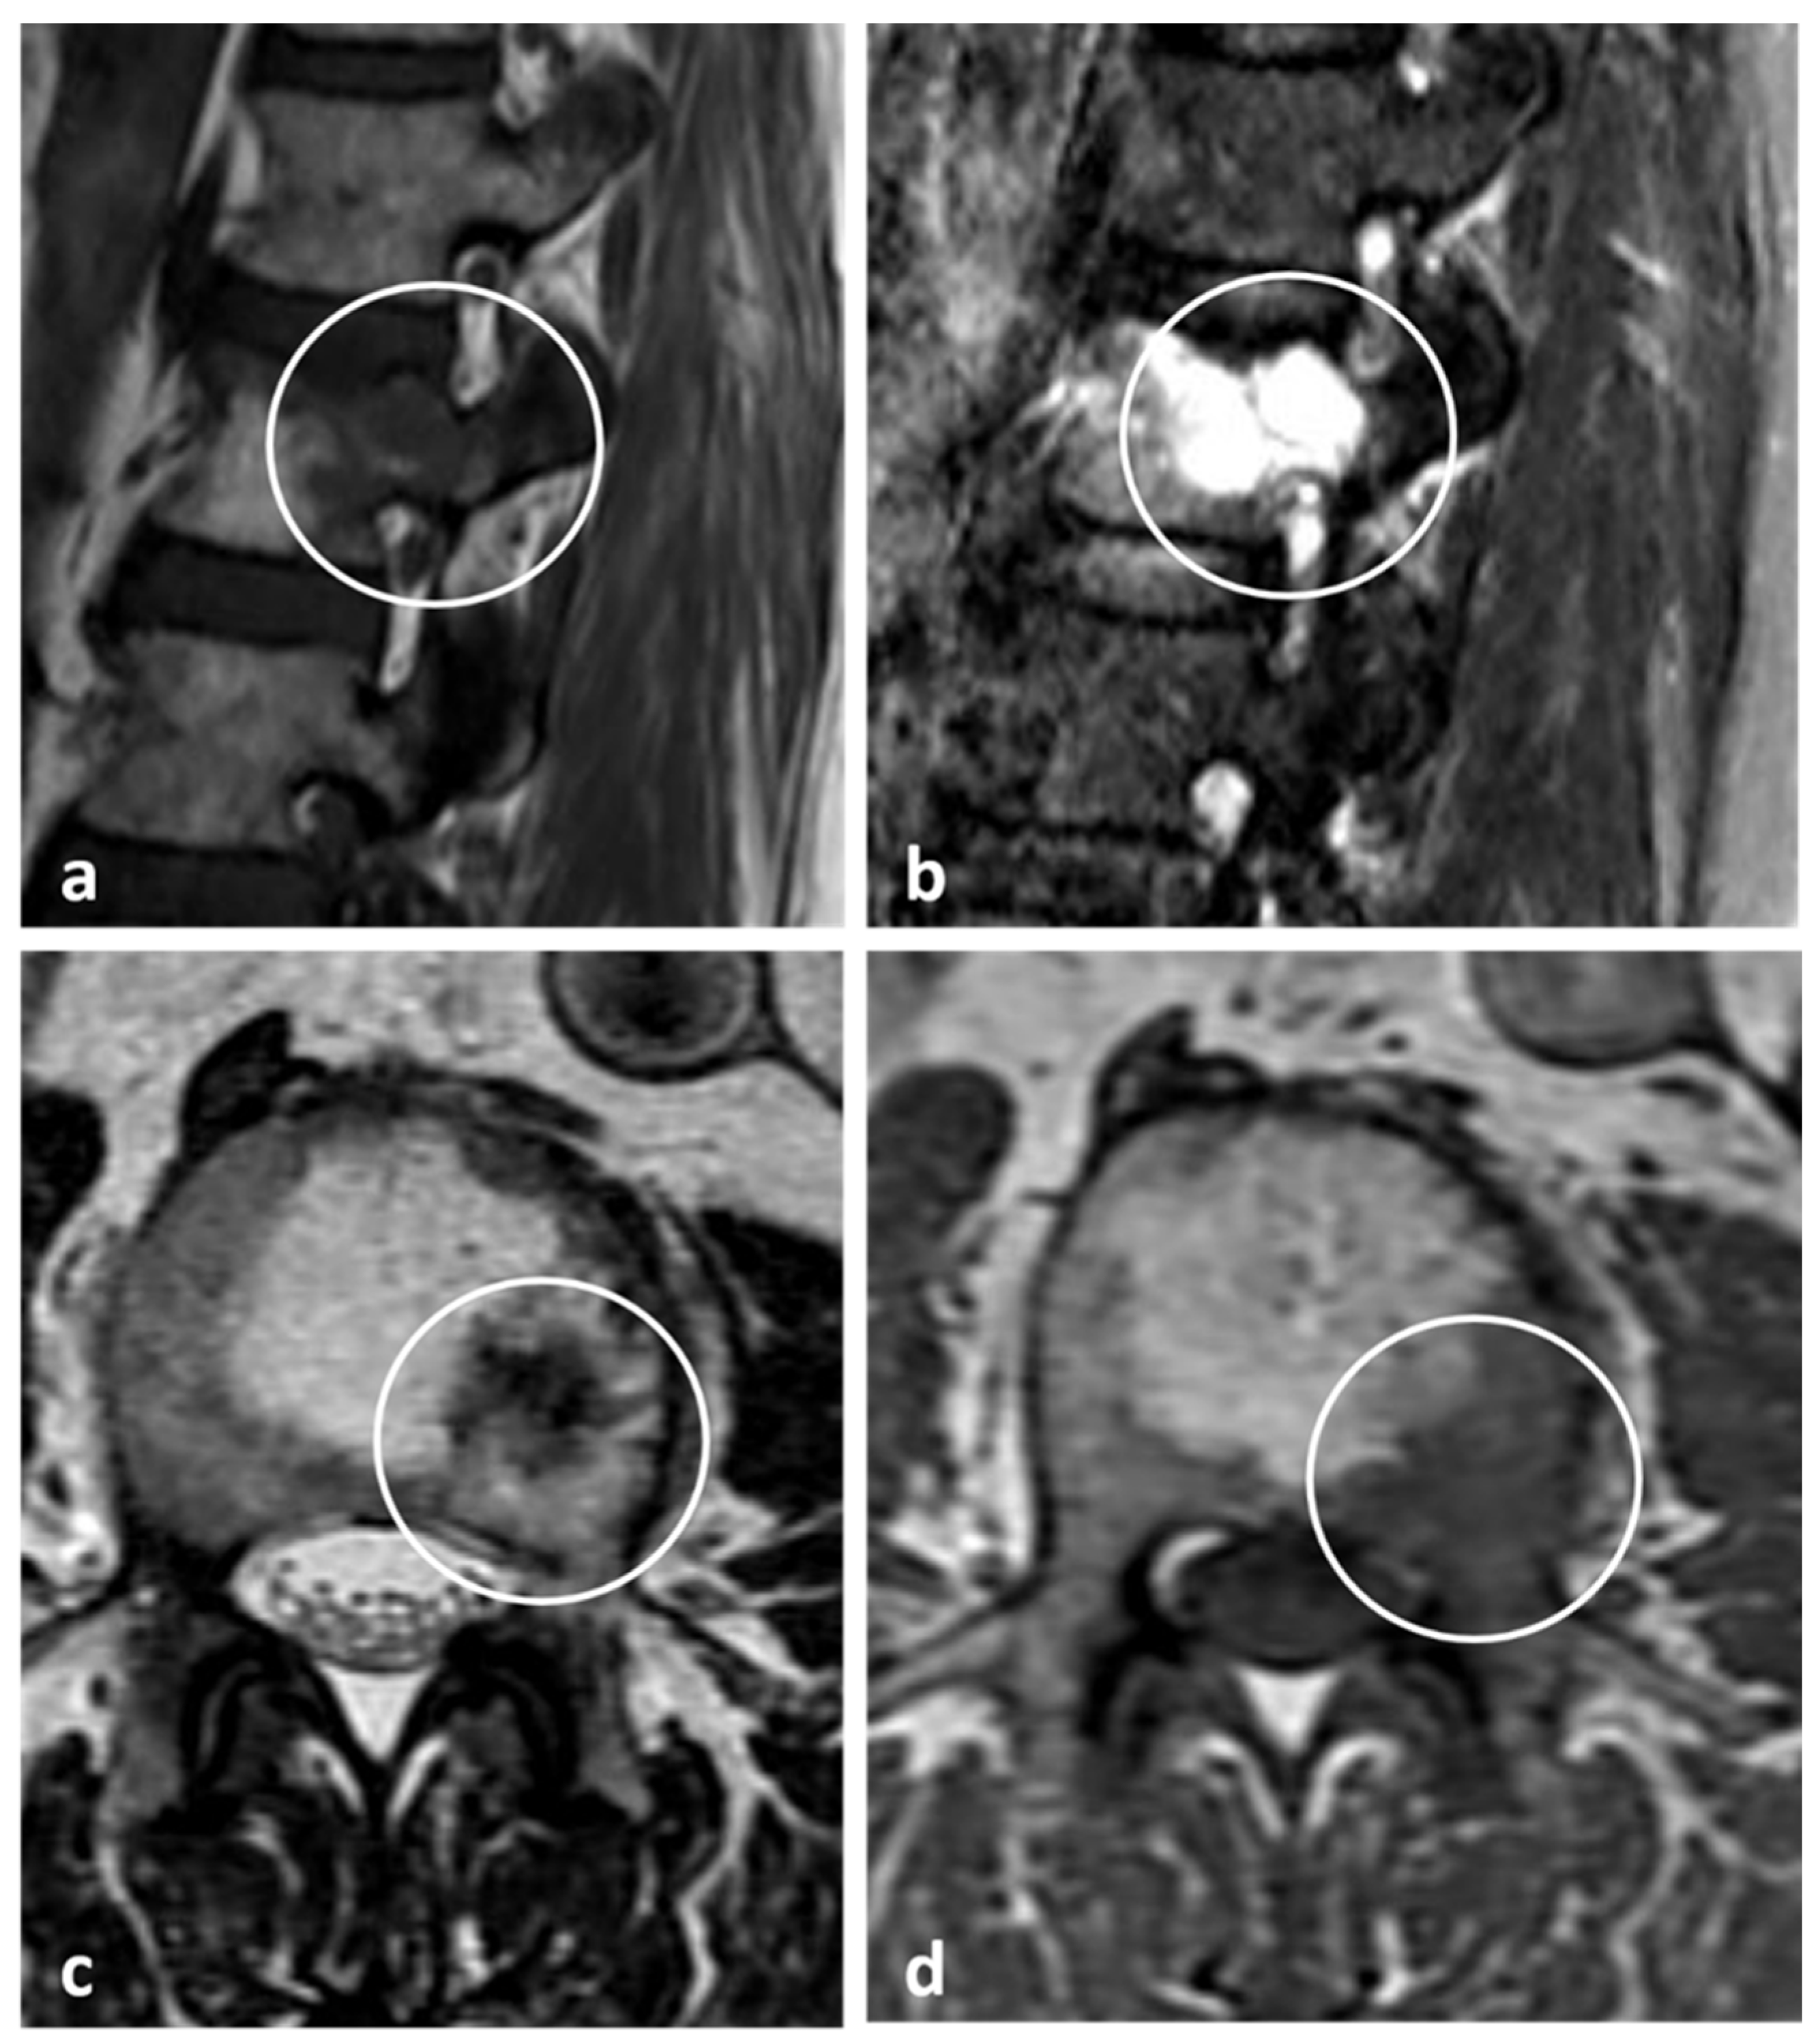

| Aneurysmal bone cyst | Expansile lytic lesion with internal bone septations. | Fluid—fluid levels within the cysts, high T1 signal within layering fluid content due to haemorrhage. |

| Giant cell tumour | Mixed cystic and solid expansile lesions, with thin peripheral bony shell. ‘Soap bubble’ appearance. | Secondary ABC change is common, with fluid—fluid levels. Intermediate to low signal intensity on both T1 and T2. Enhancing soft tissue component. |